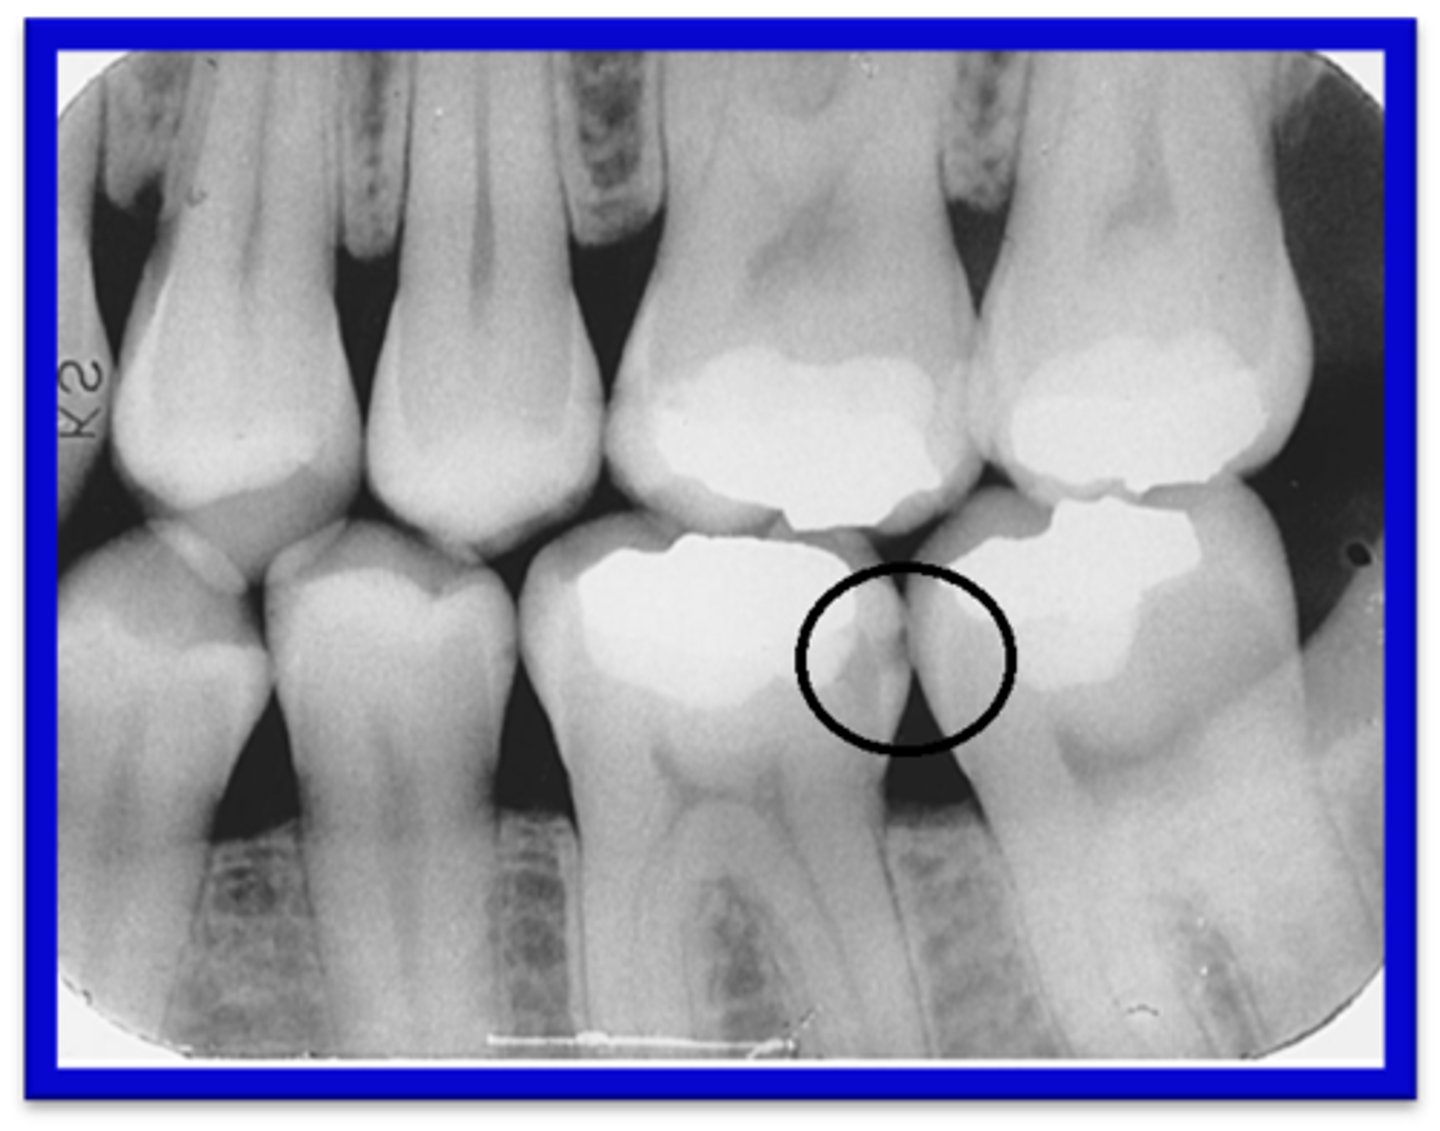

Furkation

Den yta där rötterna skiljs åt. Tänder med två eller fler rötter har alltså bara denna typ av yta.

Två rötter: bifurkation

Tre rötter: trifurkation